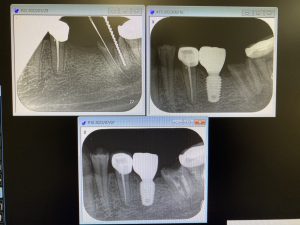

今日の収穫は、半年間仮歯を装着しながら、カルビタールを貼薬し根管治療されていた方

病巣がかなり縮小しているので MTAセメントを使い根充 病巣が大きい時は、殺菌効果の高いヨード添加のカルビタールが効きますね 特級水酸化カルシウムより、治りが早いと感じてます